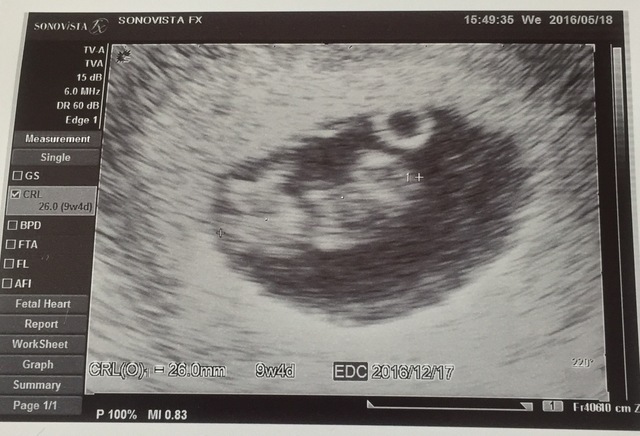

9週4日(9w4d・女の子)|トマトマトちゃん さん(27歳)

エコー写真撮影時のエピソード:

妊娠がわかって少し経って悪阻がピークだった頃。

検診後点滴をして正直妊娠なんてするんじゃなかったと思っていた時、助産師さんがこのエコー写真を点滴しているところに持ってきてくれて「赤ちゃんも大きくなってるからがんばってね!」って励まされて、母親の自覚がもてました。